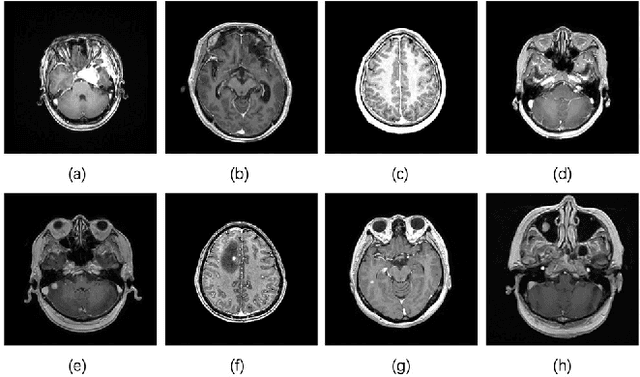

Abstract:In the clinical diagnosis and treatment of brain tumors, manual image reading consumes a lot of energy and time. In recent years, the automatic tumor classification technology based on deep learning has entered people's field of vision. Brain tumors can be divided into primary and secondary intracranial tumors according to their source. However, to our best knowledge, most existing research on brain tumors are limited to primary intracranial tumor images and cannot classify the source of the tumor. In order to solve the task of tumor source type classification, we analyze the existing technology and propose an attention guided deep convolution neural network (CNN) model. Meanwhile, the method proposed in this paper also effectively improves the accuracy of classifying the presence or absence of tumor. For the brain MR dataset, our method can achieve the average accuracy of 99.18% under ten-fold cross-validation for identifying the presence or absence of tumor, and 83.38% for classifying the source of tumor. Experimental results show that our method is consistent with the method of medical experts. It can assist doctors in achieving efficient clinical diagnosis of brain tumors.